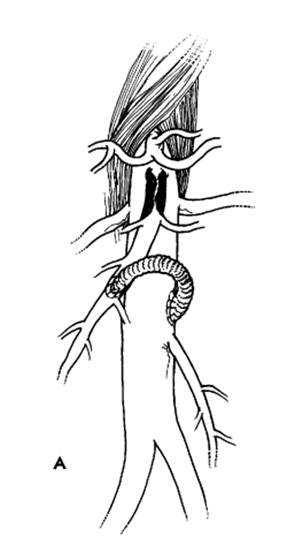

SMA embolectomy. The proximal portion of the SMA is dissected free from the surrounding fat and lymphatic tissue just as it emerges from the pancreatic neck into the base of the mesentery. Approximately 3 to 4 centimeters of artery is cleared, with care taken not to damage the branches. Heparin (5000 units) is given intravenously. A transverse arteriotomy is made and a 3F or 4F embolectomy catheter is passed proximally and distally to clear the embolus and reestablish vigorous pulsatile flow. If proximal flow cannot be established, SMA thrombosis is likely and reconstructive surgery will be required.

FIG. A - Schematic representation of revascularization of the SMA with: bypass taking care to avoid kinking and obs-

truction B - Or re-implantation of SMA into the aorta. C - Angiographic appearance of aorto-SMA bypass with vein graft.